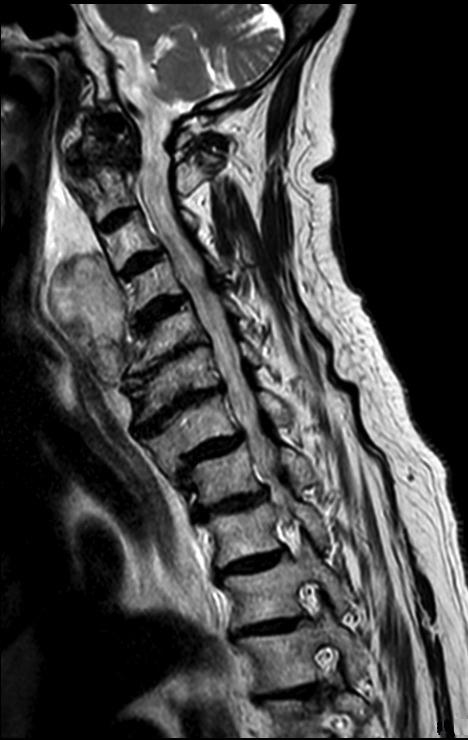

Enkele uren na een val op het hoofd krijgt een 91-jarige vrouw last van kortademigheid en een globusgevoel. Patiënte is niet buiten bewustzijn geweest en zij gebruikt geen orale antistolling. De MRI-scan toont een retrofaryngeale zwelling